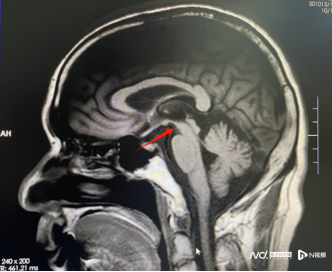

该院神经内一科副主任匡祖颖仔细询问患者病史,结合临床指征及磁共振成像提示中脑萎缩呈“蜂鸟征”,最终诊断为进行性核上性麻痹(PSP)。

MRI提示患者中脑萎缩“蜂鸟征”

“患者以行动缓慢、姿势不稳起病,陆续出现眼球运动困难、肢体僵硬及情绪不稳定等症状,是典型的PSP。”匡祖颖介绍,PSP临床症状主要包括垂直性核上性凝视麻痹、姿势不稳易摔跤、运动和认知功能障碍,影像学上则表现出特征性的“蜂鸟征”。